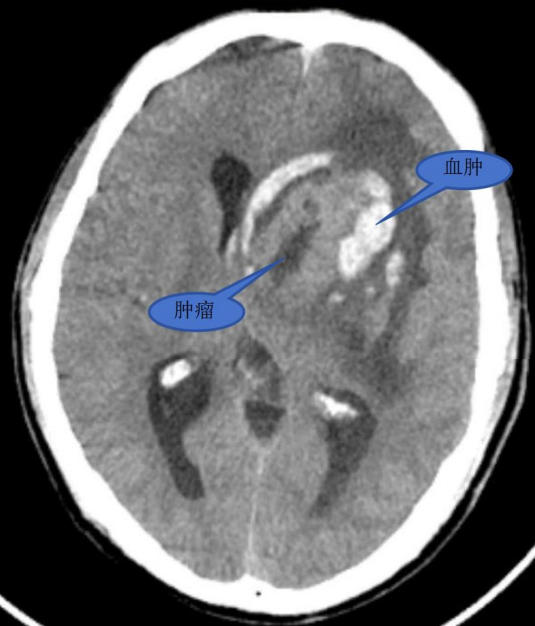

患者为 58 岁男性,因突发右侧肢体乏力 2 小时入院。急诊 CT 检查结合病史与影像学分析,诊断为脑肿瘤卒中,肿瘤大小达 4.3×3.6×2.9cm。入院后,王继斌副主任组织神经内科、肿瘤科、麻醉科、康复医学科等多学科专家,对病情及治疗方案进行深入评估讨论,获得患者及家属充分理解与支持。

术前影像